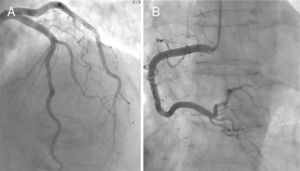

O ecocardiograma e a ventriculografia objetivaram em todos os doentes acinesia/hipocinesia segmentar apical (100%) e/ou mediana (90%), com FEVE comprometida, quantificada entre os 25-68% (Fig. 1).

O cateterismo cardíaco identificou uma lesão intermédia na descendente anterior numa doente; nos restantes, destacou-se a ausência de lesões significativas (Fig. 3). Todos os doentes desta série apresentaram bom prognóstico, como é típico da MCT, no qual está implícito o caráter de reversibilidade, não invalidando, contudo, a gravidade do quadro na situação aguda, uma vez que esta depende do grau de disfunção sistólica do VE. Houve apenas um caso complicado de choque cardiogénico.